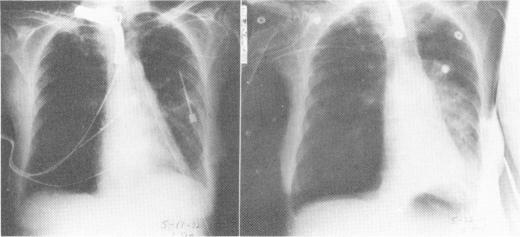

Single lung transplantation in experimental and human emphysema.

Ann Surg. 1973 Oct;178(4):463-76. doi: 10.1097/00000658-197310000-00009.